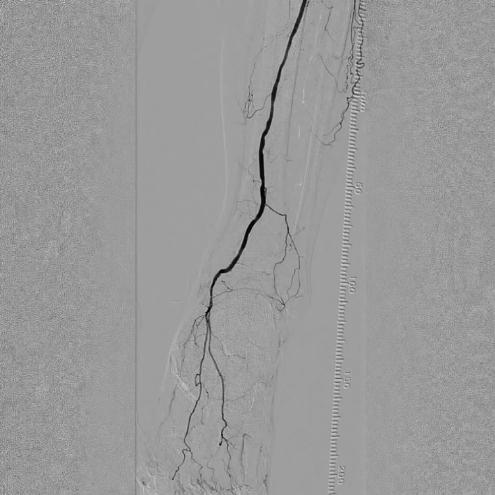

选用2×40mm普通球囊扩张闭塞病变,造影可见局部内膜撕裂严重,形成明显夹层(提示病变坚硬,需支架支撑)。

造影显示:胫腓干动脉血流恢复通畅,支架形态及位置理想,胫后动脉显影较术前明显改善;